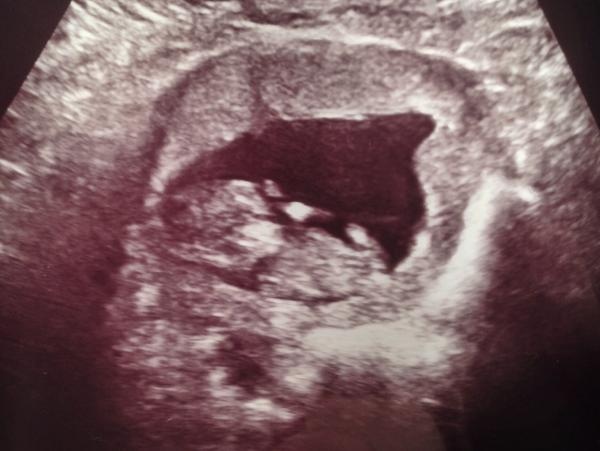

Jag och min sambo väntar vårt första barn kring månadsskiftet juli-augusti. Idag var vi på privat UL och fick se det lilla livet och samtidigt dra en lättnadens suck, för ibland har jag trott att jag bara hittat på allt :P

Enligt senaste mens är jag i v 11+6 och enligt UL 11+4 :) När barnmorskan bad mig hosta för att väcka pyret så sträckte den på sig och kröp ihop till en liten boll - ett magiskt ögonblick!